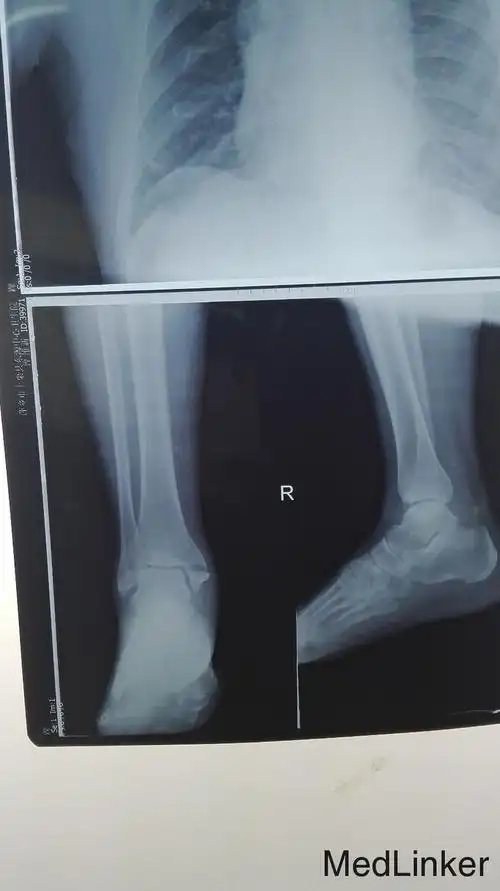

胫骨内侧髁骨折

右脚内踝骨折,有uu帮忙看看这个伤的严重吗